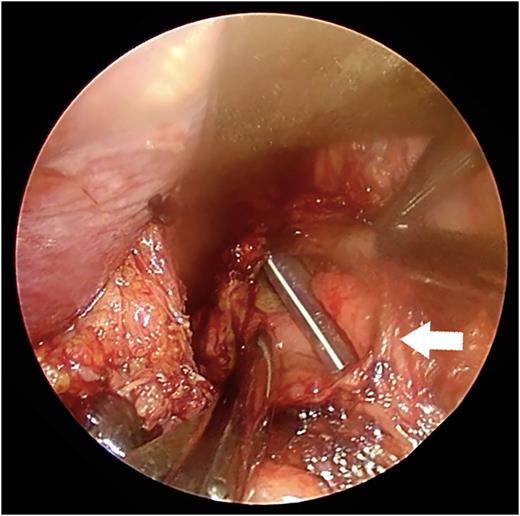

A 67-year-old man presented with vomiting and epigastric pain. He had a history of duodenal ulceration and emergent laparotomies for repeated duodenal perforation, resulting in stenosis of the second portion of the duodenum. The patient was referred to our hospital for evaluation of vomiting. He exhibited upper abdominal guarding on physical examination. His blood chemistry revealed no abnormal findings with the exception of a mild increase in the C-reactive protein level (2.1 mg/dl). His nutritional state was maintained. Dynamic computed tomography revealed massive right pleural effusion with pneumomediastinum. A defect was present in the lower esophagus, his stomach was dilated and the proximal duodenal wall was thickened (Fig. 1a and b). Thoracoscopic exploration was performed prior to laparotomy in the left semi-lateral decubitus position with 2 ports under differential lung ventilation. The right pleural cavity was severely contaminated with brownish pleural effusion and was thus irrigated under thoracoscopy, but the perforated site was not identified. Laparotomy was then performed, which revealed a 4-cm longitudinal defect on the right side of the lower esophagus via esophageal hiatus (Fig. 2). The defect was closed by direct suturing with 4-0 pieces of monofilament strings and reinforced by using the greater omentum. The surgical field was irrigated, and a feeding jejunostomy was created. A 19F blake drain (Ethicon, Inc., Sommerville, NJ, USA) was placed in the lower mediastinal space via abdominal cavity, and a 20F thoracic drain (Sumitomo Bakelite Co., Ltd, Tokyo, Japan) was placed in the right thoracic cavity via the port site. The position of the mediastinal drain was cranially adjusted using the thoracoscopy (Fig. 3a and b). Extubation and enteral feeding via the jejunostomy tube were initiated on Day 2. Endoscopic dilatation was performed due to esophageal stenosis. The patient was discharged on Day 60 without mediastinitis, pneumonia or empyema.

A picture of the perforated site. A nasogastric tube was found via the perforated site during transabdominal manipulation (arrow).